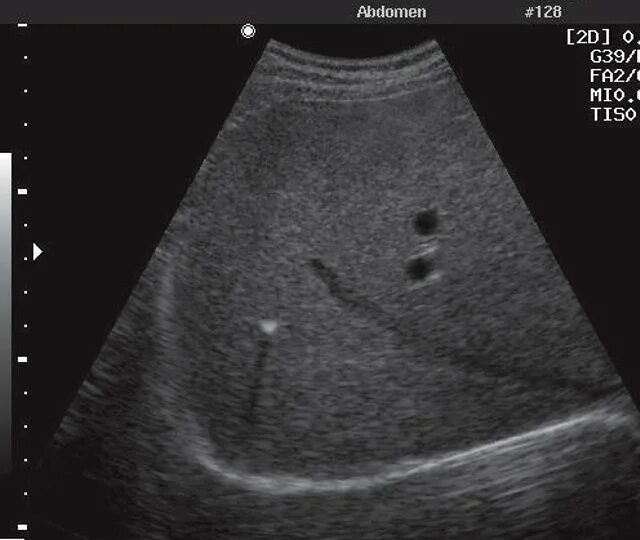

Уменьшение селезенки